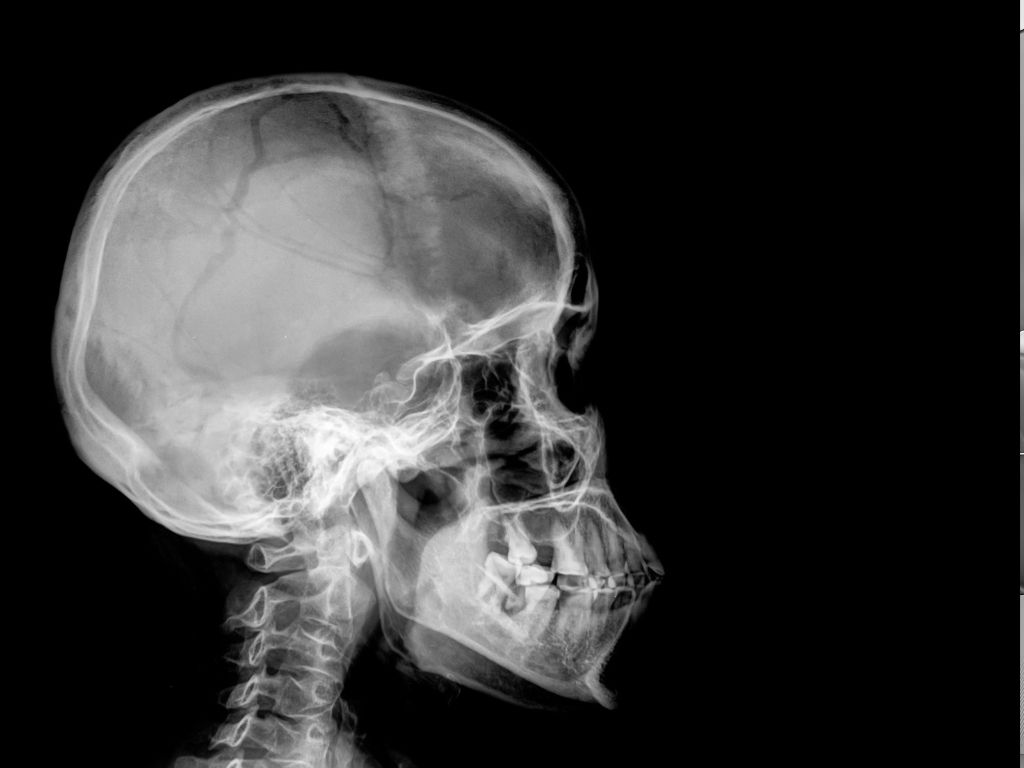

Рентген кісток черепа – один із базових та найінформативніших методів обстеження, який дозволяє швидко оцінити стан кісткових структур, виявити травми, патологічні зміни та контролювати динаміку лікування.

Що показує рентген кісток черепа

Це дослідження дозволяє виявити:

переломи та тріщини кісток черепа;

вдавлені або багатоуламкові травми;

зміщення кісткових структур;

ознаки остеомієліту;

пухлиноподібні утворення кісток;

вроджені дефекти;

патології приносових пазух;

запальні процеси та ускладнення після травм.

Цифрова технологія дозволяє отримати максимально чіткі знімки, що значно підвищує точність діагностики.